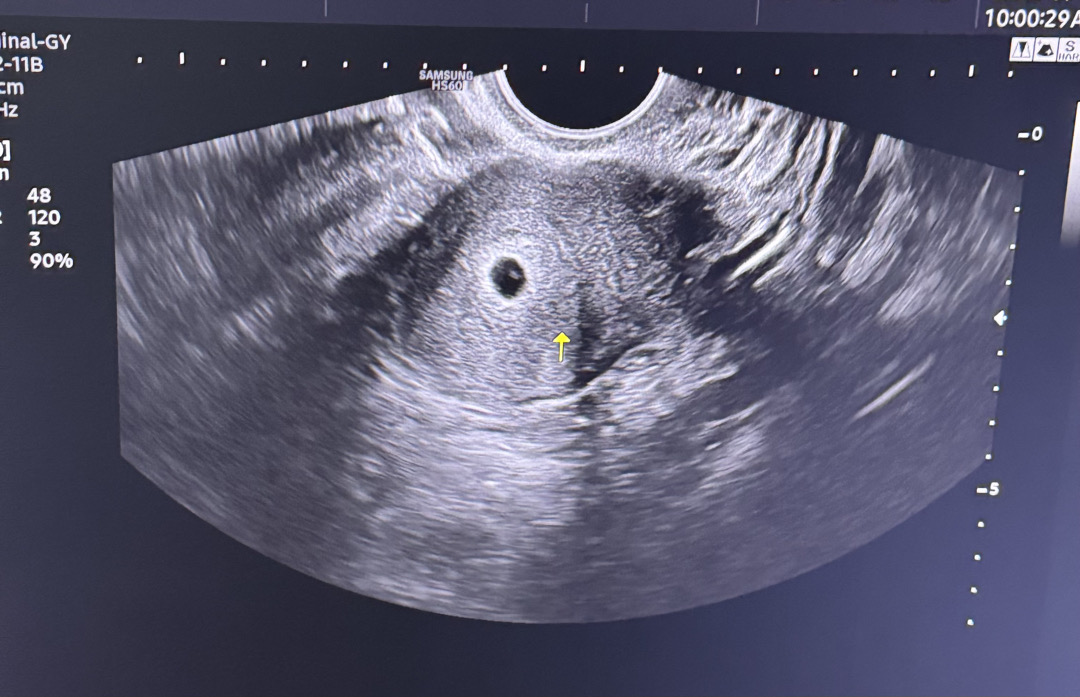

5주0일차(5일배아 이식17일차) 아기집이랑 난황 봤어요! 모양 어떤가요ㅠㅠ? 다음주 월요일 6주0일차에 아기, 심장소리도 들을수있을까용..?!

저도 22일 5주0일차 초음파 봤는데 비슷해요 아기집 9mm에 난황 작게 봤어요 ㅎㅎ